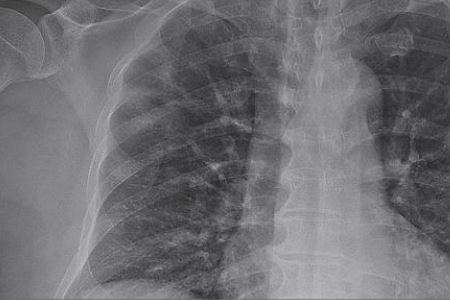

现在已经进入3月份了,距离新型冠状病毒感染的肺炎出现,已经过去了好几个月了。很多人估计的心里还有是在害怕,担心疫情会变严重。小编提醒,根据公布是数据得知,全国各地每天新增的病例已经减少许多,还有许多地方已经半个多月没有新增的病例。建议多关注相关的消息,缓解心中的焦虑。下面就来看看截至3月8日24时新型冠状病毒肺炎疫情最新情况吧。

3月8日0—24时,31个省(自治区、直辖市)和新疆生产建设兵团报告新增确诊病例40例,新增死亡病例22例(湖北21例,广东1例),新增疑似病例60例。当日新增治愈出院病例1535例,解除医学观察的密切接触者3802人,重症病例减少153例。

截至3月8日24时,据31个省(自治区、直辖市)和新疆生产建设兵团报告,现有确诊病例19016例(其中重症病例5111例),累计治愈出院病例58600例,累计死亡病例3119例,累计报告确诊病例80735例,现有疑似病例421例。累计追踪到密切接触者674760人,尚在医学观察的密切接触者20146人。

湖北新增确诊病例36例(武汉36例),新增治愈出院病例1422例(武汉1163例),新增死亡病例21例(武汉18例),现有确诊病例18303例(武汉16627例),其中重症病例4991例(武汉4735例)。累计治愈出院病例46433例(武汉30933例),累计死亡病例3007例(武汉2388例),累计确诊病例67743例(武汉49948例)。新增疑似病例28例(武汉28例),现有疑似病例277例(武汉253例)。

3月8日0—24时,新增报告境外输入确诊病例4例(甘肃4例)。截至3月8日24时,累计报告境外输入确诊病例67例。累计收到港澳台地区通报确诊病例169例:香港特别行政区114例(出院59例,死亡3例),澳门特别行政区10例(出院10例),台湾地区45例(出院15例,死亡1例)。(注:“信息来自国家卫生健康委员会官方网站”。)